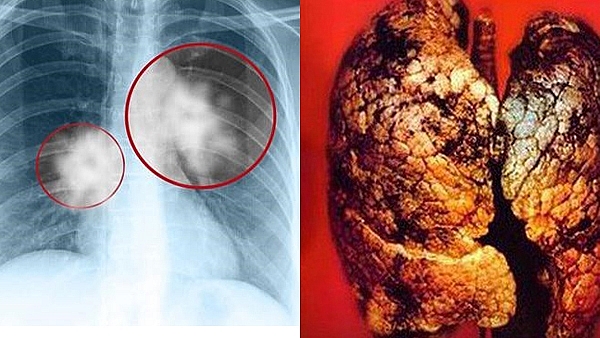

Khối u di căn não là một trong những khối u nội sọ khá phổ biến ở người lớn, chiếm trên 50% tổng số các loại u não. Đối với bệnh nhân ung thư nói chung, ung thư phổi nói riêng, di căn lên não là một biến chứng thường gặp. Di căn não chiếm khoảng 40-50% các trường hợp bệnh nhân ung thư phổi.

Di căn vào não là một trong những khu vực nguy hiểm nhất mà tế bào ung thư phổi có thể lan tỏa đến, đe dọa nghiêm trọng tính mạng của người bệnh. Theo nghiên cứu của Đại học McMaster (Canada), việc di căn vào não thường xảy ra phổ biến và thường diễn ra trong giai đoạn 4 của bệnh (giai đoạn cuối).